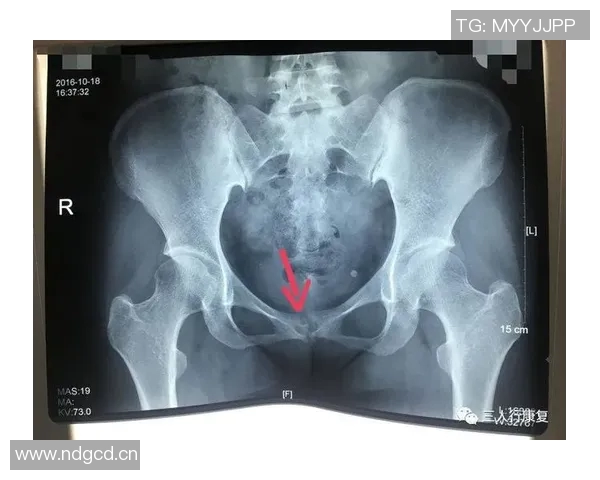

尼科·威廉姆斯是一名备受瞩目的年轻球员,他在比赛中表现出色,为球队贡献了许多关键进球。然而,在一次重要比赛中,他不幸遭遇了耻骨炎。这种疾病给他的训练和比赛造成了严重影响,让他不得不面对漫长而艰难的恢复过程。

初期,尼科并没有意识到自己的伤势有多严重。他依旧坚持参加训练,但随着时间推移,他逐渐感受到身体的不适。经过专业医生的检查后,他被确诊为耻骨炎,这让他深感沮丧,因为这意味着他需要停下脚步,进行长时间的康复治疗。